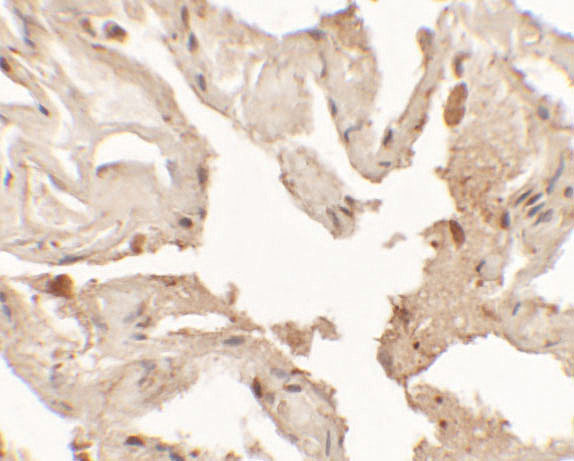

May play a role in lung development and surfactant homeostasis. Types a regulatory loop with GRHL2 that coordinates lung epithelial cell morphogenesis and differentiation.

Thyroid and lung.